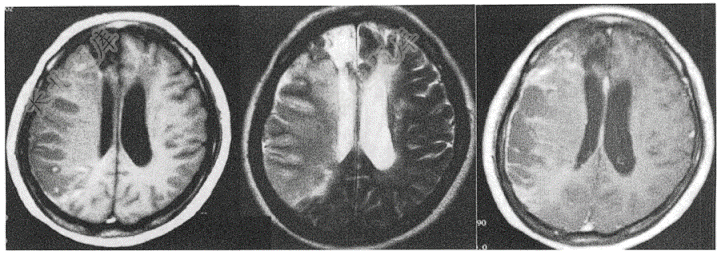

- 单项选择题患者男,46岁,头颅MR如下,请问患者诊断考虑为( )

A、右侧颞叶脑梗死

B、右侧额顶叶脑梗死

C、右侧颞叶脑出血

D、右侧额顶叶脑出血

E、右侧基底节脑梗死